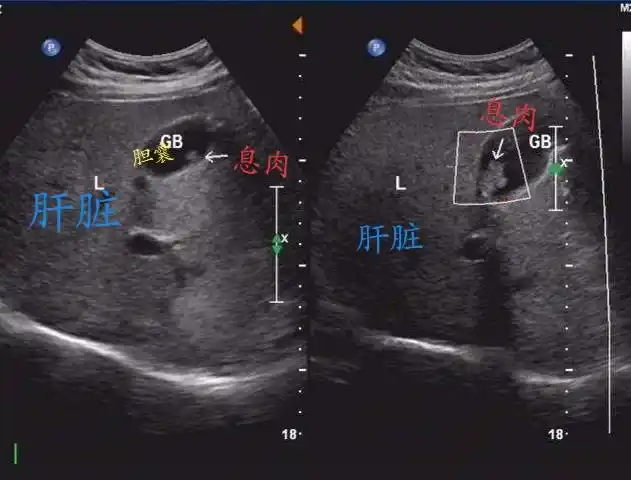

让人费解的胆囊息肉 - 超声医学讨论版 - 爱爱医医学论坛 - 爱爱医

胆囊息肉,看了忘不了 - 超声医学讨论版 - 爱爱医医学论坛